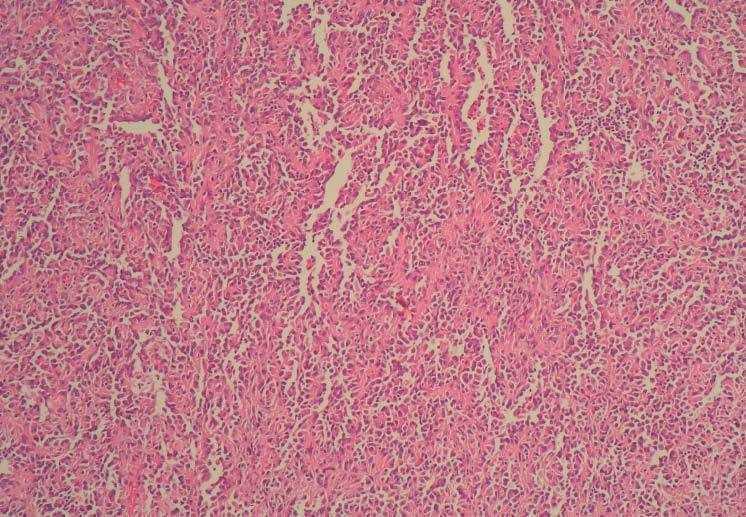

Figura 2. Tinción hematoxilina-eosina. Canales vasculares anastomosados y dilatados con proliferación de células endoteliales atípicas.

En la histopatología hay proliferación de células endoteliales atípicas con proyecciones papilares hacia la luz, que forman canales vasculares irregulares con tendencia a anastomosarse, tapizados por una o varias capas de células. Las células tumorales infiltran disecando fibras de colágeno y tejido adiposo. Los cuerpos de Weibel Palade están ausentes y los marcadores CD31, CD34, antígeno relacionado con el factor VIII y Ulex europaeus aglutinina son positivos4.